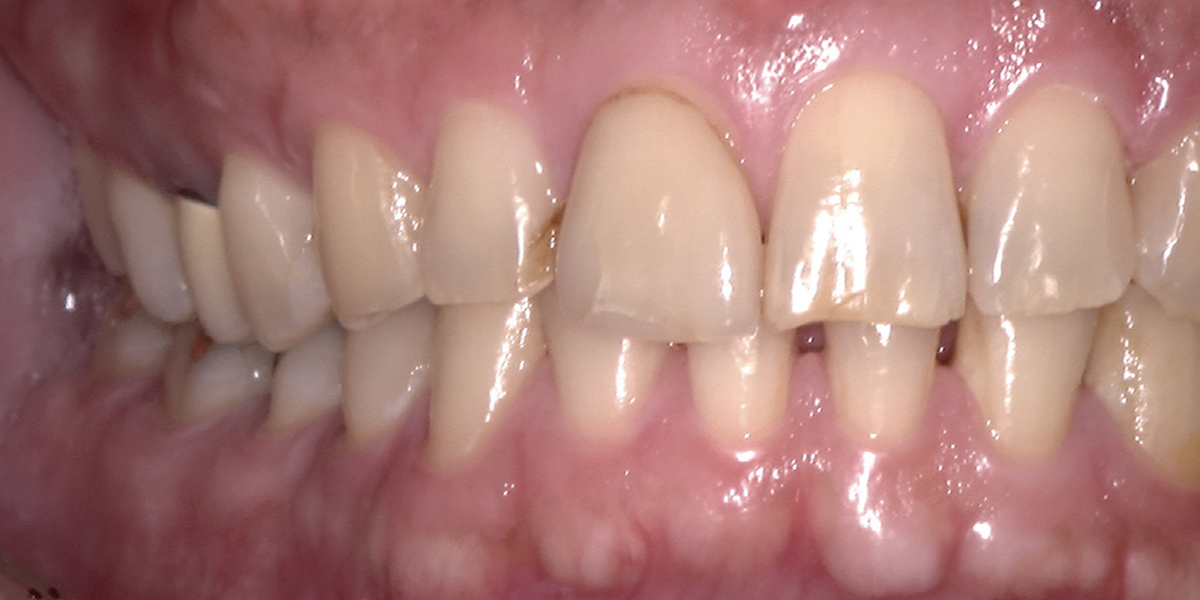

鮮明・インパクト画像で説明を

拡大しても鮮明で見やすいインパクトのある画像で説明を行えば、 患者さんの関心度・満足度が向上します。医院スタッフの教育にも活用できます。